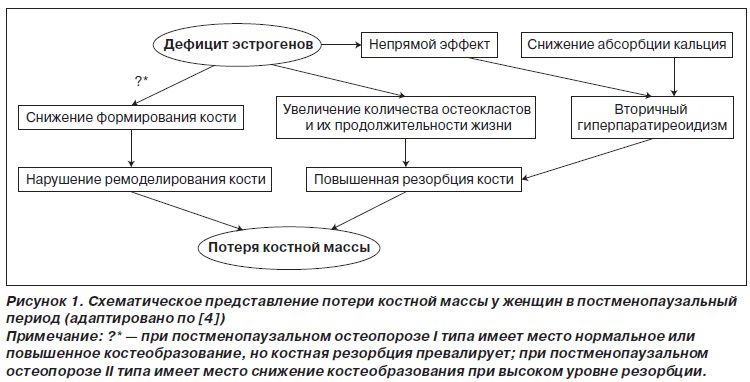

Вторая половина XX века ознаменовалась созданием новой группы препаратов — бисфосфонатов, рекомендованных для лечения остеопороза и других метаболических заболеваний. Бисфосфонаты широко используются в лечении постменопаузального остеопороза, характеризующегося прогрессивной потерей губчатой кости, связанной с дефицитом эстрогенов, который проявляется прямым и непрямым воздействием на костную ткань (рис. 1). Прямое действие при недостатке эстрогенов связано с нарушением остеобластической функции — пула остеобластов и их метаболической активности, что приводит к снижению формирования кости. Увеличение активности остеокластов сопровождается повышением резорбции кости. Это способствует нарушению баланса костного ремоделирования. Непрямой эффект эстрогенов связан со снижением абсорбции кальция и повышением биосинтеза паратгормона. Суммарное действие этих факторов приводит к снижению костной массы.